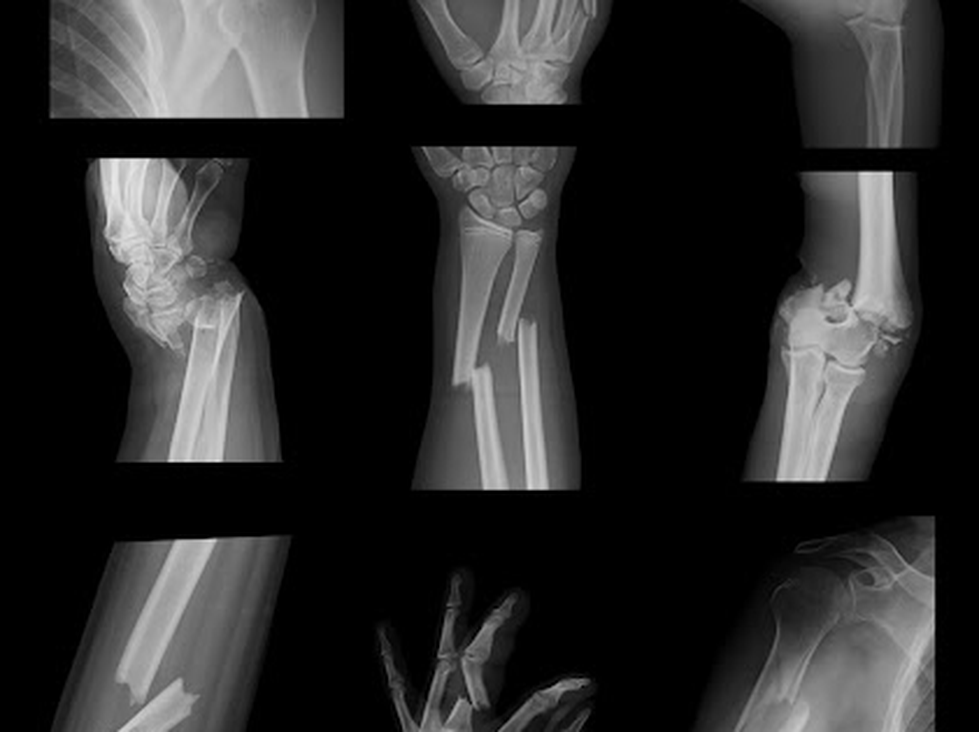

Chụp X quang để xác định gãy xương;

Nghi ngờ gãy xương dựa trên các triệu chứng và kết quả khám sức khỏe, nhưng cần phải có hình ảnh (thường là chụp X quang) để khẳng định.

Nếu cần, chụp X quang thường quy trước.

Chụp X-quang thường quy cho thấy xương chủ yếu (và tràn dịch khớp thứ phát sau chảy máu hoặc gãy xương ẩn) và do đó rất hữu ích để chẩn đoán gãy xương. Bao gồm ít nhất 2 hình được chụp ở các hướng khác nhau (thường là phía trước và bên).